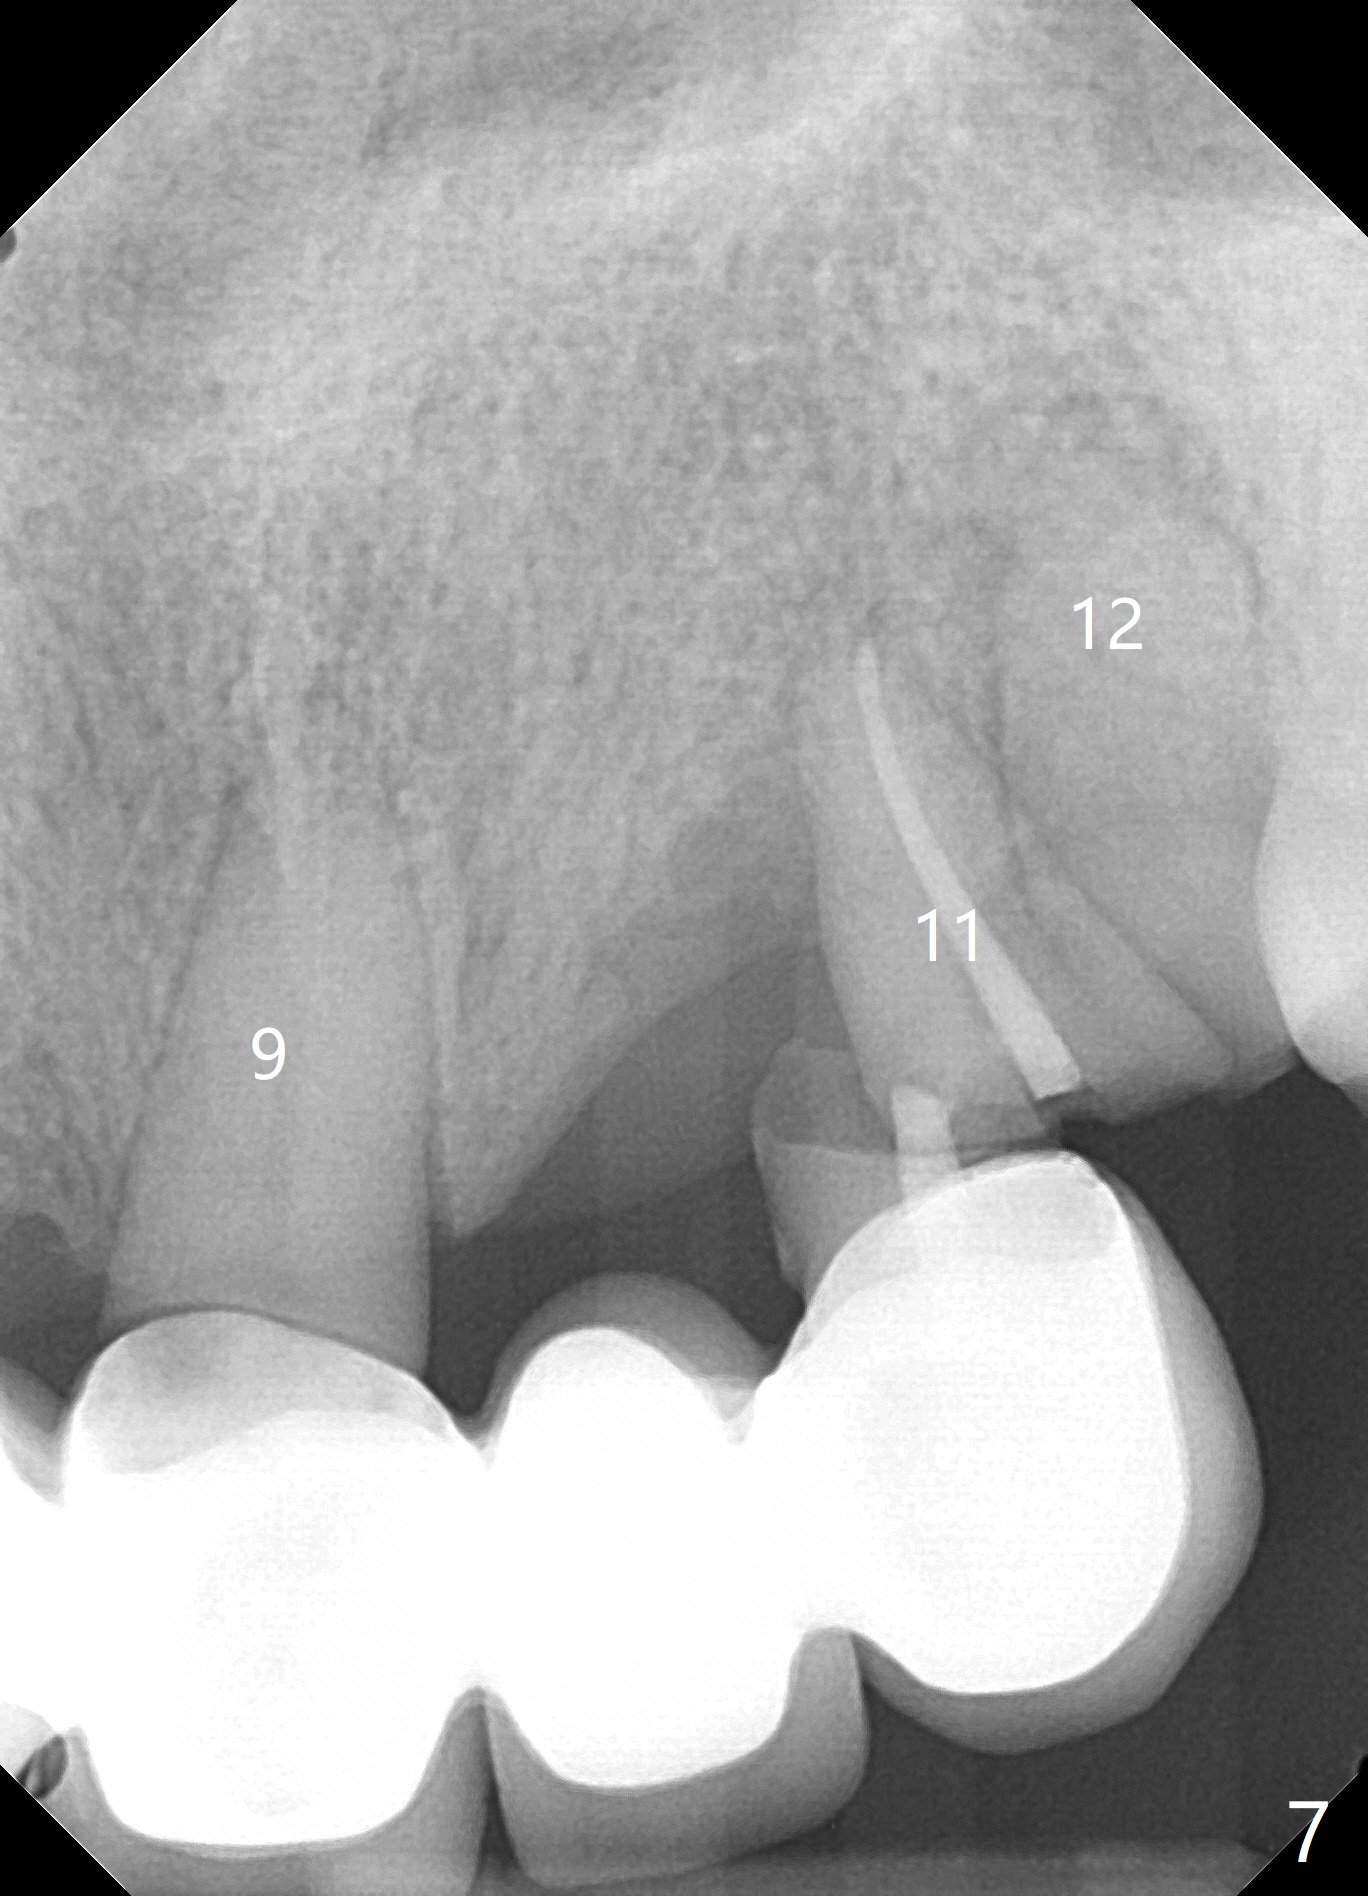

A 71 year old lady has issue with an upper bridge (#7-11, Fig.5-7). While one of the abutments (anchor teeth for FPD), #7, is "tender", the other (#11) fractures. Take Alginate impression (upper and lower) when she returns, pour models (no bubbles, 1 U, 2 L), and keep U Alginate for provisional. Section FPD at #7 and 9, take 12x9 cm CT with 2 cotton rolls and full arch impression for guide with bite registration. Prepare Endo Ice for #7 (tenderness). Tell the patient and her daughter that the lower left cantilever FPD is in bad shape, since the tooth #19 has large furca radiolucency (Fig.4 *). Next appointment should be scheduled for SRP (Fig.1-4).